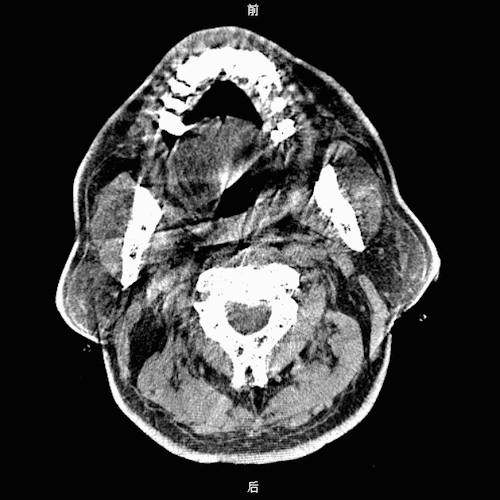

CT提示脑干、双侧基底节区、脑室旁腔隙腔梗灶。

颈动脉CTA显示右侧大脑中动脉M1段闭塞,右侧颈内动脉开口处中度狭窄,右侧颈内动脉C6段、左侧颈内动脉C4段动脉瘤待排。